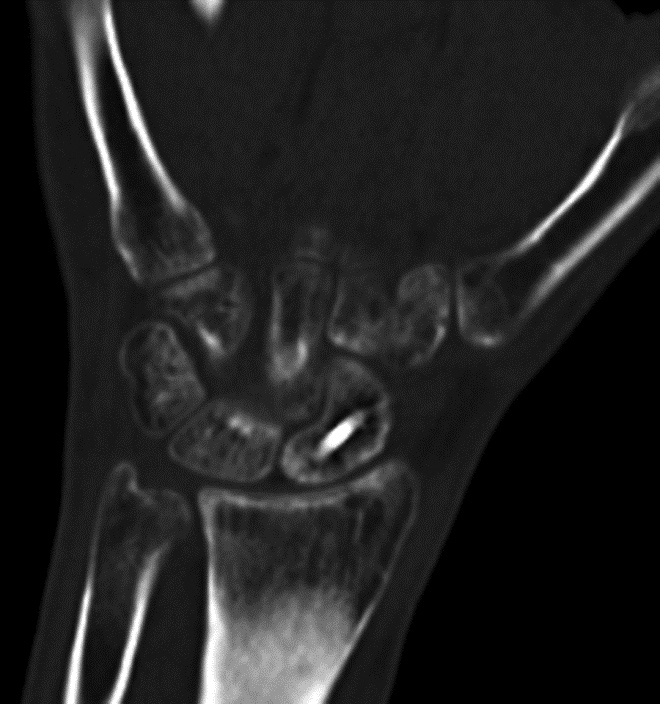

Fracture healing and joint fusion may be assessed readily with radiographs, but the presence of callus formation alone does not predict progression to complete healing, and the presence of osseous bridging is considered a more reliable indicator of union (Figure 9) (Ohashi, 2009). CT has been found to be more accurate for the determination of osseous bridging, as radiographs may either underestimate or overestimate the extent of bone fusion (Krestan, 2006; Grigoryan, 2003). The presence of exuberant callus formation may obscure the evaluation for osseous bridging on radiographs, and multiplanar CT allows direct visualization of the fracture site. In addition, fine central osseous bridging at the site of small fractures and bone grafts, such as in treated, non-united scaphoid fractures, is better assessed with thin slice CT images (Figure 10). Finally, some articulations are difficult to assess due to overlapping anatomy, such as the posterior subtalar and Lisfranc joints, and CT offers superior delineation of the joint spaces following arthrodesis.

Figure 9A Figure 9B Figure 10A Figure 10B

Fracture union Fracture union Scaphoid fracture Scaphoid fracture

Scaphoid Fracture Evaluation. (A) Sagittal multiplanar reformation shows central portion of compression screw in the scaphoid with incomplete union at periphery of fracture site (arrowheads). Note absence of streak artifact due to small size of screw. (B) Coronal multiplanar reformation shows fracture union at the central portion of the scaphoid waist, indicating partial union.